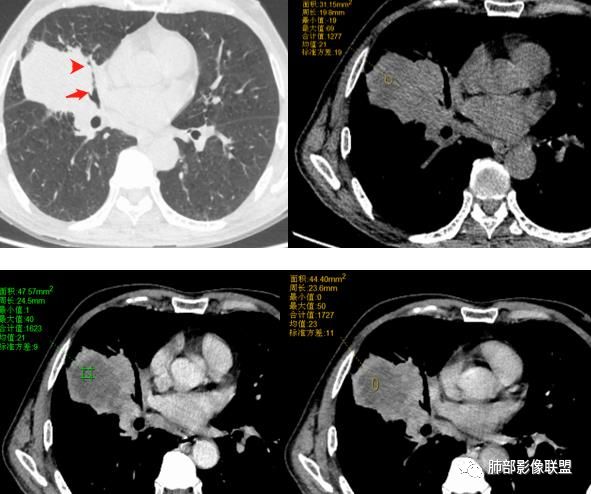

右肺中叶可见类圆形软组织密度肿块影,右肺中叶外侧段支气管狭窄截断。肿块密度不均,边缘毛燥不规则,可见毛刺。远侧肺内可见网格条索影。增强后可见不均匀强化。纵隔淋巴结肿大,部分融合。考虑右肺恶性病变,鳞癌>腺癌,并纵隔淋巴结转移。

右肺巨大肿块,横跨上中下三叶,主体在中叶,外侧段近端支气管截断,膨隆分叶,毛刺,网格,淋巴结大,不均匀强化,湖泊样坏死,考虑恶性,低分化鳞癌>腺

右肺肿块,横跨上中下三叶,主体在中叶,外侧段近端支气管截断,膨隆分叶,毛刺,网格,淋巴结大,不均匀强化,有坏死,鳞癌?

右肺跨上叶与中叶一实性肿块影,中叶外侧段支气管堵塞,肿块有明显分叶、毛刺、棘突样改变,胸膜牵拉,周围有小花小草;增强可见病灶明显强化,病灶内可见大片状低密度区,以外侧为主,隆突下可见肿大淋巴结,恶性,考虑鳞癌可能。

老年男性,体检发现右肺巨大肿块,右肺跨叶生长,可见支气管截断,边缘见分叶,毛刺,右肺支气管不通,增强后边缘强化,内部示大片低密度坏死区,边界不清,周围肺组织小叶间隔增厚,纵隔见多发肿大淋巴结。考虑为恶性并淋巴结转移。

老年男性,右肺不规则跨叶肿块,有分叶,相邻支气管阻断,强化不均有低密度坏死区,坏死区边界较清,类似湖泊样,内见血管穿行,造影征,病灶远端可能有阻塞性炎症,总体考虑鳞癌。

右肺中叶巨大肿块,外侧段近端支气管截断,横跨上中下三叶,主体在中叶,膨隆分叶,毛刺,网格,淋巴结大,不均匀强化,伴阻塞性肺炎及肺不张,湖泊样坏死,考虑恶性,鳞癌可能性较大

右肺中叶肿块影,向上向下侵犯叶间裂,边缘膨隆,分叶,毛刺。肿块内部密度不均,大片坏死。血管走形尚可。中叶支气管狭窄截断。增强不均匀强化。纵隔淋巴结肿大,部分融合。

考虑恶性,腺癌>鳞癌。鉴别炎肌母。

晨读:右中为主肿块,跨叶,右中叶外侧支闭塞,病灶有坏死,远侧少许小叶间隔增厚,考虑恶性,腺癌大于鳞癌。结合有无吸烟史

1.本病例结合病理结果及影像综合分析,应该符合肉瘤样癌,上皮成分是腺癌为主;肿块的边缘毛刺、分叶及周围癌型淋巴管炎征象有符合腺癌的影像表现之处。

2.肿块巨大局部边缘膨隆、光整,坏死较彻底;明显跨叶生长(途经发育不全叶间裂或肺门,注意患者没有胸水),支气管阻塞伴推移等,这些更符合肉瘤的特性。

3.坏死区边界较清楚(皮囊样),环形强化明显,病灶内血管穿行等,都不符合我们常见的鳞癌。